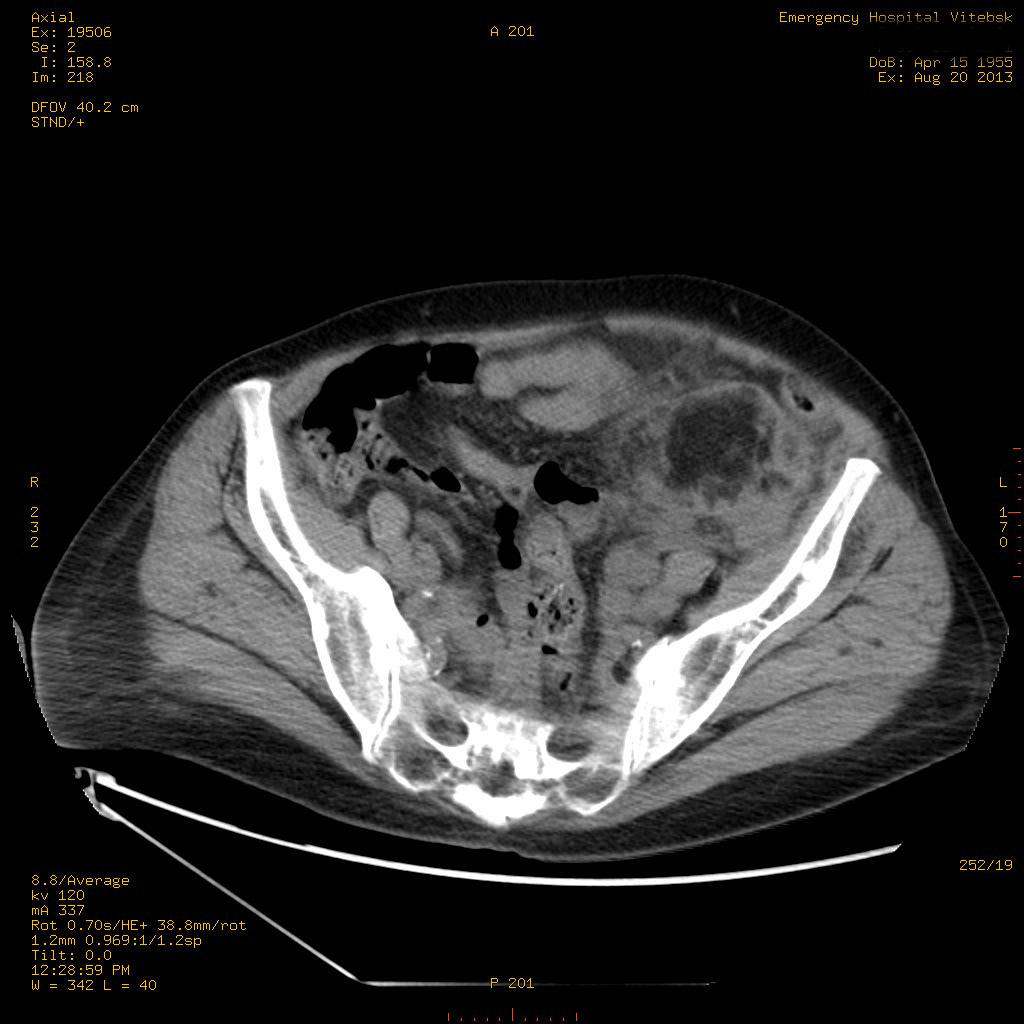

Пожилая женщина с нормальными мочевиной и креатинином.

se000.jpg

se001.jpg

se002.jpg

se003.jpg

se004.jpg

se005.jpg

se006.jpg

se007.jpg

se008.jpg

se009.jpg

se010.jpg

se011.jpg

se012.jpg

se013.jpg

se015.jpg

Ангиомиолипоматоз почек , думаю компонент туберозного склероза.

Да, туберозный склероз.

Случай консультирован на кафедре радиологии Католического университета г.Лёвен (Бельгия) - зав каф. профессор Р.Оуен.